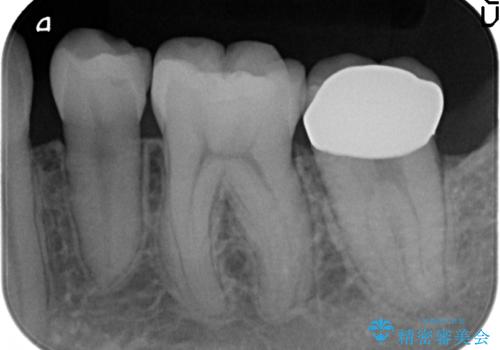

その後歯茎の治りを待ちポケットが正常値であることを確認後、オールセラミッククラウンによる補綴を行いました。

今回用いたオールセラミッククラウンはジルコニアフレームという白い素材の上にセラミックを盛っているため、審美性が非常に高いのが特徴です。

また、ジルコニアは人工ダイヤモンドの材料にも使われているほど高い強度を持っており、そのためオールセラミッククラウンは審美性だけでなく、奥歯やブリッジの補綴も可能とするクラウンです。